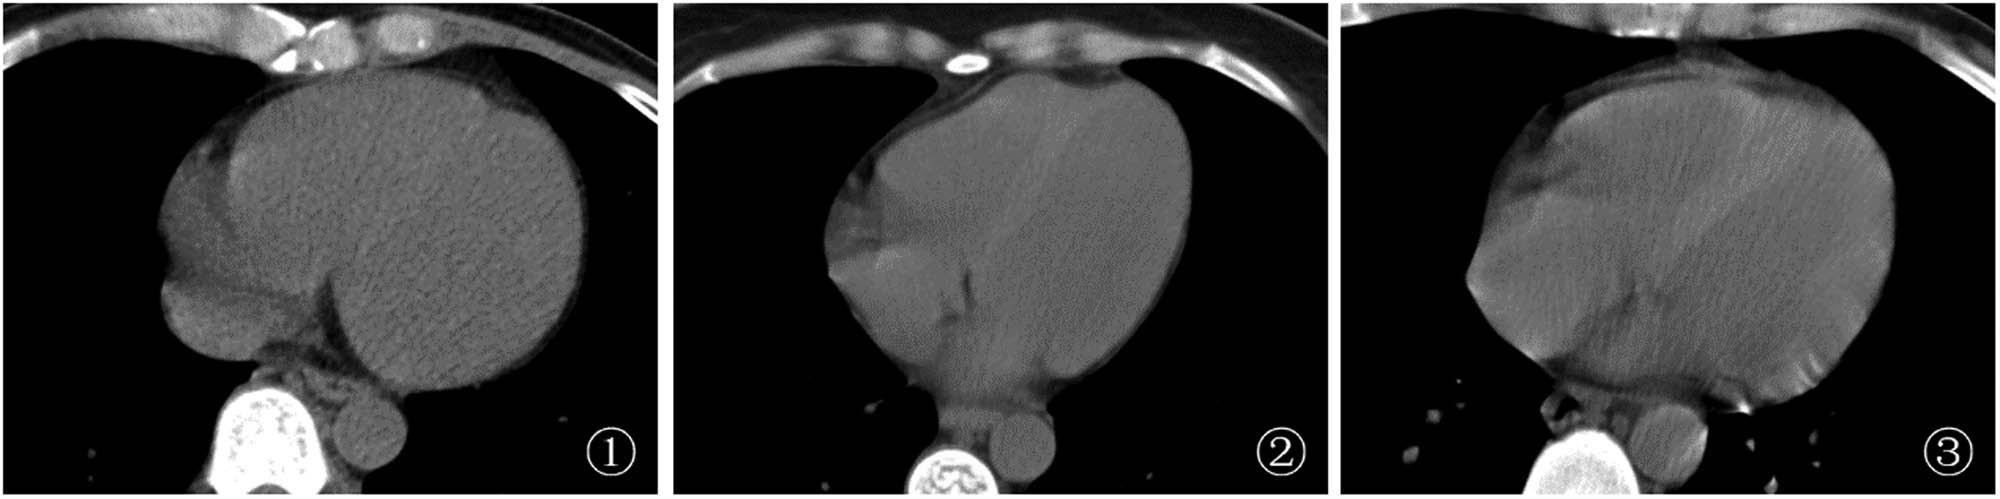

LVD and RVD of HIV-infected patients with anemia were lower than those of VSD (Figure 1). In the mild anemia group, the mean LVD, RVD, and VSD were 38.90 ± 6.19 HU, 39.74 ± 9.66 HU, and 49.55 ± 6.95, respectively, with a median VSD/LVD of 1.29 (1.20–1.38) and a median VSD/RVD of 1.22 (1.11–1.37); in the moderate anemia group, the mean LVD, RVD, and VSD were 34.54 ± 8.11 HU, 34.99 ± 8.73 HU, and 47.72 ± 7.05, respectively, with a median VSD/LVD of 1.34 (1.26–1.57) and a median VSD/RVD of 1.36 (1.24–1.53); in the severe anemia group, the mean LVD, RVD, and VSD were 32.19 ± 7.23 HU, 34.25 ± 7.92 HU and 49.04 ± 5.98, respectively, with a median VSD/LVD of 1.46 (1.37–1.63) and a median VSD/RVD of 1.40 (1.27–1.6).

Chest CT images of a HIV-infected patient with anemia (1) A male patient, 44 years old, with mild anemia, HB = 109 g/L, LVD and RVD slightly lower than VSD; (2) A female patient, 42 years old, with moderate anemia, HB = 77 g/L, LVD and RVD lower than VSD; (3) A male patient, 46 years old, with severe anemia, HB = 40 g/L, LVD and RVD significantly lower than VSD.

LVD and RVD in the mild anemia group were higher than those in the moderate anemia group and the severe anemia group, and VSD/LVD was lower than that in the moderate anemia group and the severe anemia group, with statistically significant differences (P < 0.05). VSD/RVD in the mild anemia group was lower than that in the moderate anemia group, with a statistically significant difference (P < 0.05); VSD/LVD in the moderate anemia group was lower than that in the severe anemia group, with a statistically significant difference (P < 0.05) (Table 2).